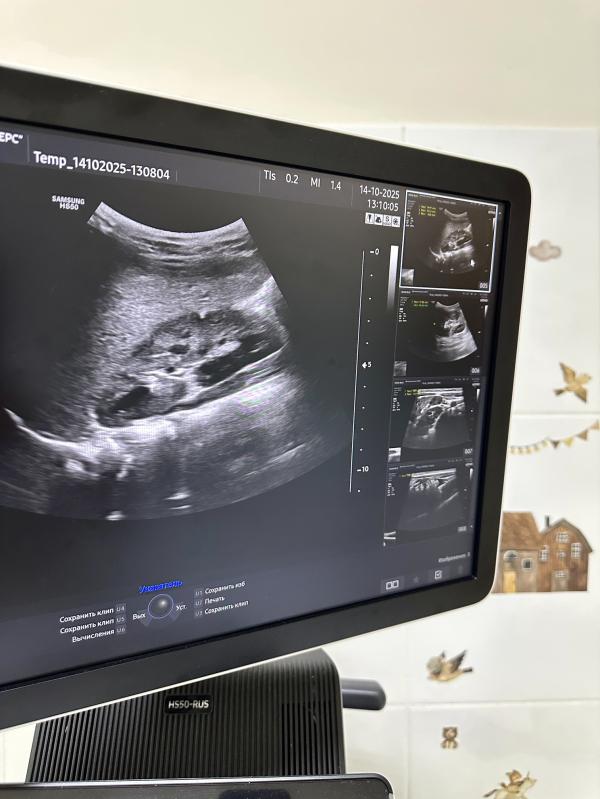

Что такое УЗИ почек и почему оно так важно?

✅ Это безопасный и точный диагностический метод, который помогает врачам увидеть внутреннюю структуру почек вашего малыша, оценить их размер, положение и возможное наличие отклонений.